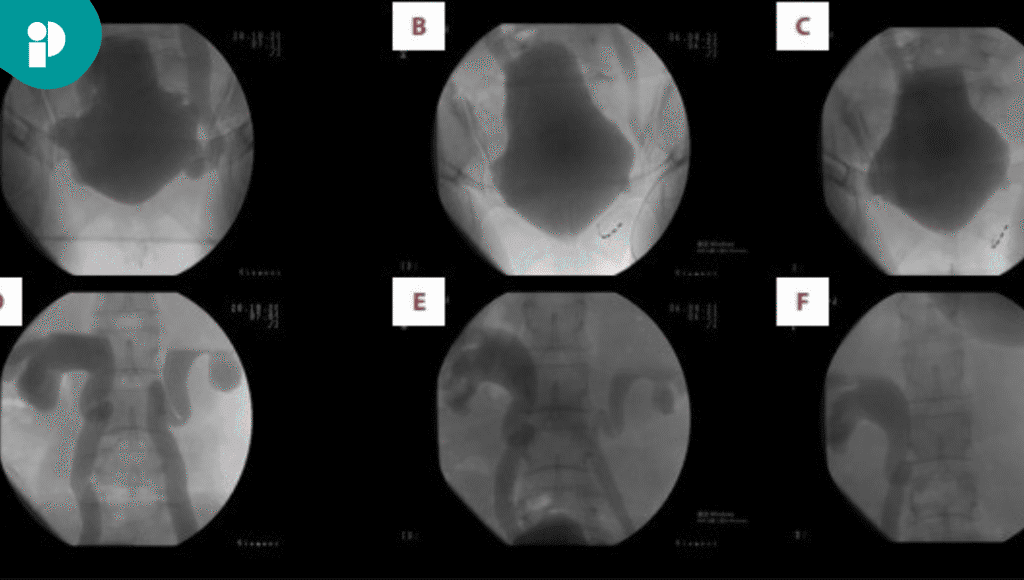

Un estudio videourodinámico confirmó la presencia de reflujo ureteral bilateral de grado IV-V y una reducción importante en la capacidad de distensión de la vejiga. Para estabilizar la situación, se colocó un catéter permanente durante tres meses, lo que permitió una mejoría parcial de la función renal.

El tratamiento logró restaurar la función del tracto urinario inferior, facilitando el almacenamiento y vaciado de orina a baja presión. Cuatro años después de la intervención, la paciente mantiene niveles normales de creatinina (75 µmol/L), sin signos de hidronefrosis en los estudios de imagen y con volúmenes de orina residual normales. Además, los análisis de orina no muestran anomalías.